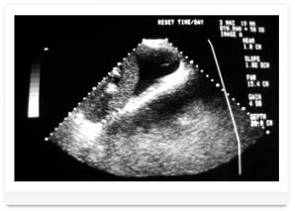

УЗИ печени. Данные, полученные при сборе анамнеза, клиническом и

лабораторном исследовании зачастую не дают четкого представления о состоянии

печени. Тогда на помощь приходит ультразвуковая диагностика, которая позволяет

выявить диффузные поражения паренхимы печени (гепатит, гепатоз, цирроз),

новообразования, механические поражения. На рисунке представлен результат УЗИ с

асцитом печени у собаки.